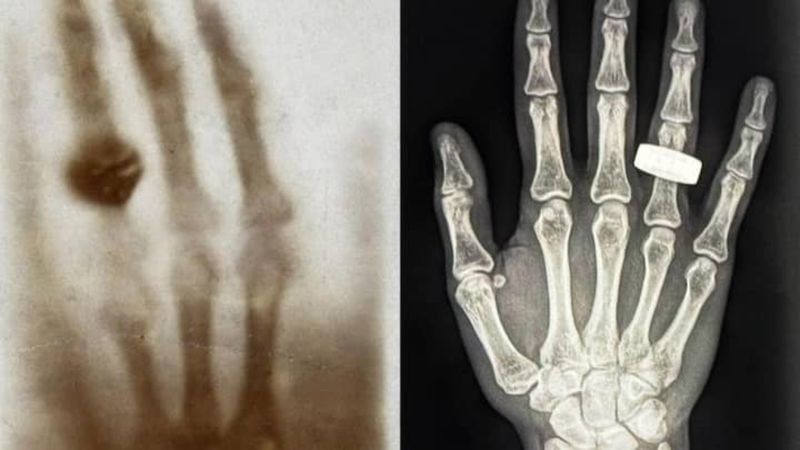

Uzayda çekilen ilk tıbbi röntgen, Fram2 görevinde gerçekleştirildi. Bu görüntü, yüzük takan bir elin gri tonlamalı taramasını içeriyor ve Wilhelm Roentgen'in 130 yıl önce çektiği orijinal röntgen filmini andırıyor.